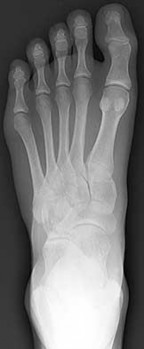

Question 10

A 30-year-old female sustains a midfoot injury after falling from a horse. Radiographs demonstrate diastasis between the bases of the 1st and 2nd metatarsals. In a normal anatomic state, the native Lisfranc ligament originates and inserts on which two bony structures?

Explanation

The Lisfranc ligament is a stout, obliquely oriented intra-articular ligament that acts as the primary stabilizer of the second tarsometatarsal joint complex. It connects the lateral aspect of the medial cuneiform to the medial aspect of the base of the second metatarsal. Importantly, there is no direct ligamentous connection between the bases of the first and second metatarsals.